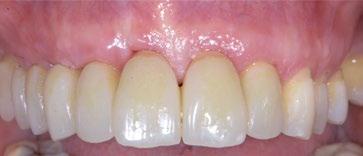

Paciente mujer de 35 años, con amplia exposición gingival en sonrisa y alta demanda estética (Fig. 1, 2).

Su solicitud inicial es volver a blanquear el 21, que había sido previamente endodonciado y había recibido sucesivos tratamientos blanqueadores que habían recidivado. Refiere ligera molestia en la papila interincisiva. En la exploración radiográfica intraoral 1 2

Tras 4 meses (Fig. 20, 21), se inicia la fase final de acondicionamiento mediante adición de composite a la corona provisional, presionando sobre el tejido ya maduro hasta modelar la emergencia simétrica a su contralateral, durante 2 meses más (Fig. 22).

A los 6 meses ya se puede proceder a realizar la corona definitiva. En este caso la paciente se decide a alinear y blanquear sus dientes antes, así que se realiza una nueva corona provisional ya que la inicial realizada con su diente natural se está oscureciendo.

Este abordaje permite conseguir una estabilidad del implante y de los tejidos duros y blandos, y un resultado estético óptimo (Fig. 25, 26, 27, 28). 